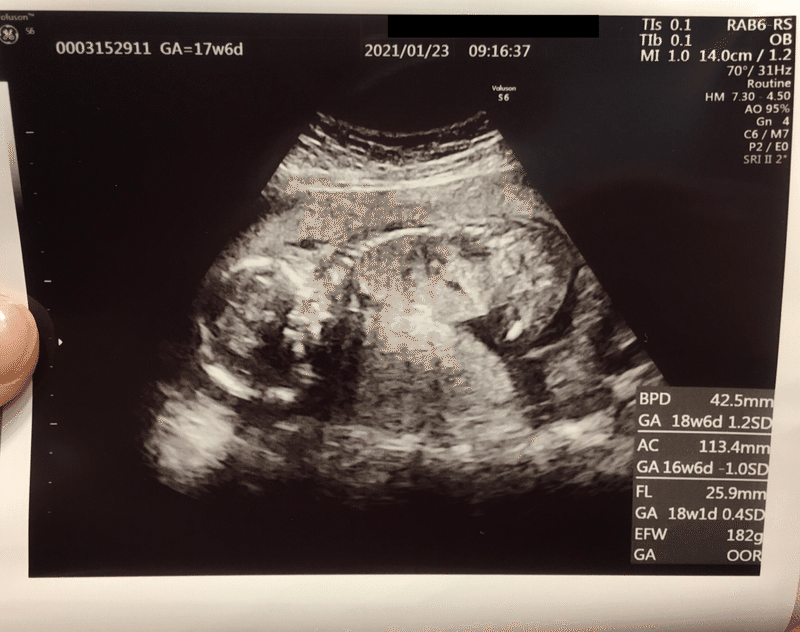

Oct 14, 18 · そしてbpd・ac・flなどから赤ちゃんのefw(推定体重)が算出されるのです。 私の場合は妊娠14週まではcrlの計測があり、以降はbpd・ac・flの計測になりました。 お持ちのエコー写真を見てみると、ga(妊娠週数)という表記があるかもしれません。Sep 03, 10 · 妊娠26週の妊婦です!エコー写真の週数のズレについて質問です。 bpd 67 26週 fl 501 28週 fta 307 24週 とバラバラで、トータルの平均が25週3日でした。 ftaが二週間小さい事が気になります。先生には何も言われなかったので家に帰ってから気が付きました。Oct 29, · 産婦人科医監修|エコー写真にはさまざまな情報が詰まっているため、見方を覚えておくと赤ちゃんの成長の様子がしっかりと確認できます。妊娠週数や計測した数値をあらわすアルファベットの意味、胎児の成長に合わせた妊娠週数ごとの写真の見え方、エコー検査でわかることを解